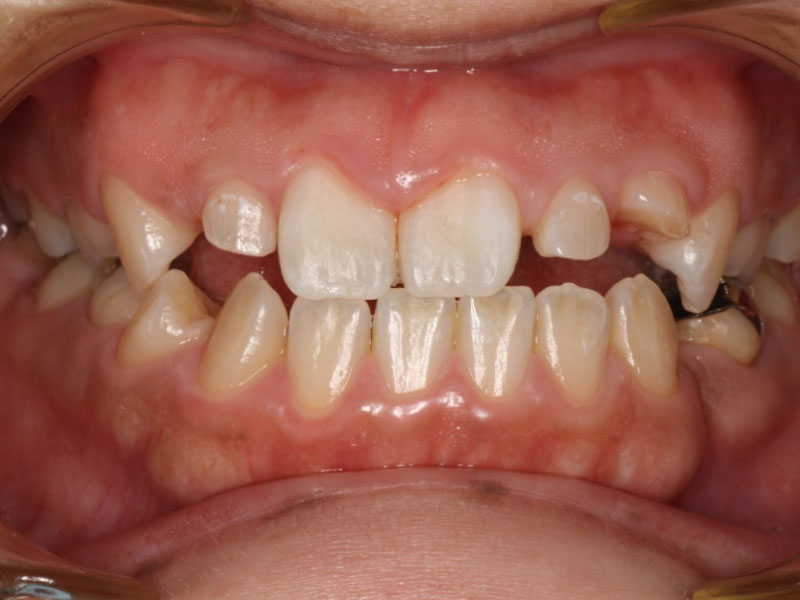

▼ ケース5 下顎前歯部叢生症例

初診時口腔内写真

初診時X線写真

治療終了時

before

after